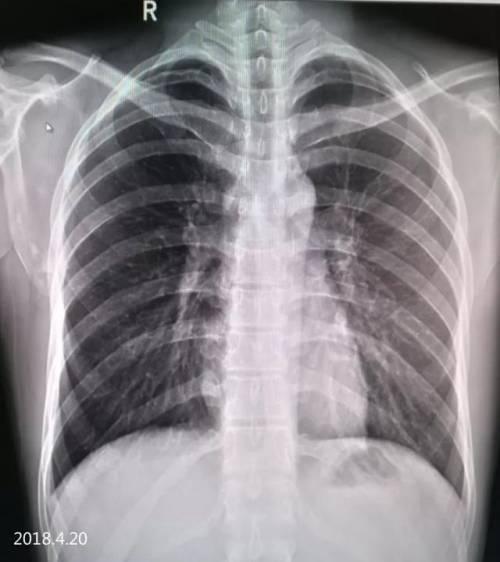

4.17 气胸复张,右下肺见液平面已吸收

气液平面x线图片

气胸x线胸片图解